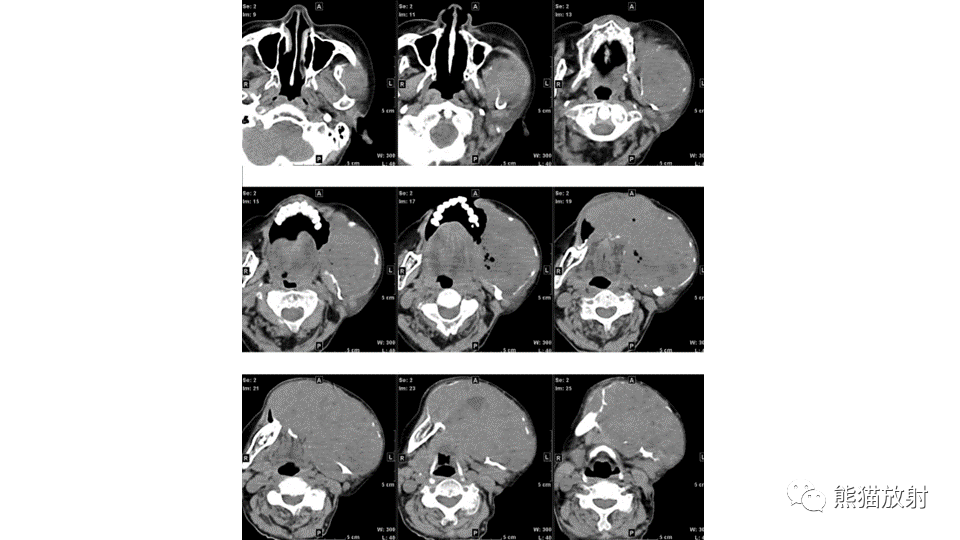

【病例】下颌骨成釉细胞瘤2例CT-1

【病例】下颌骨成釉细胞瘤2例CT-2